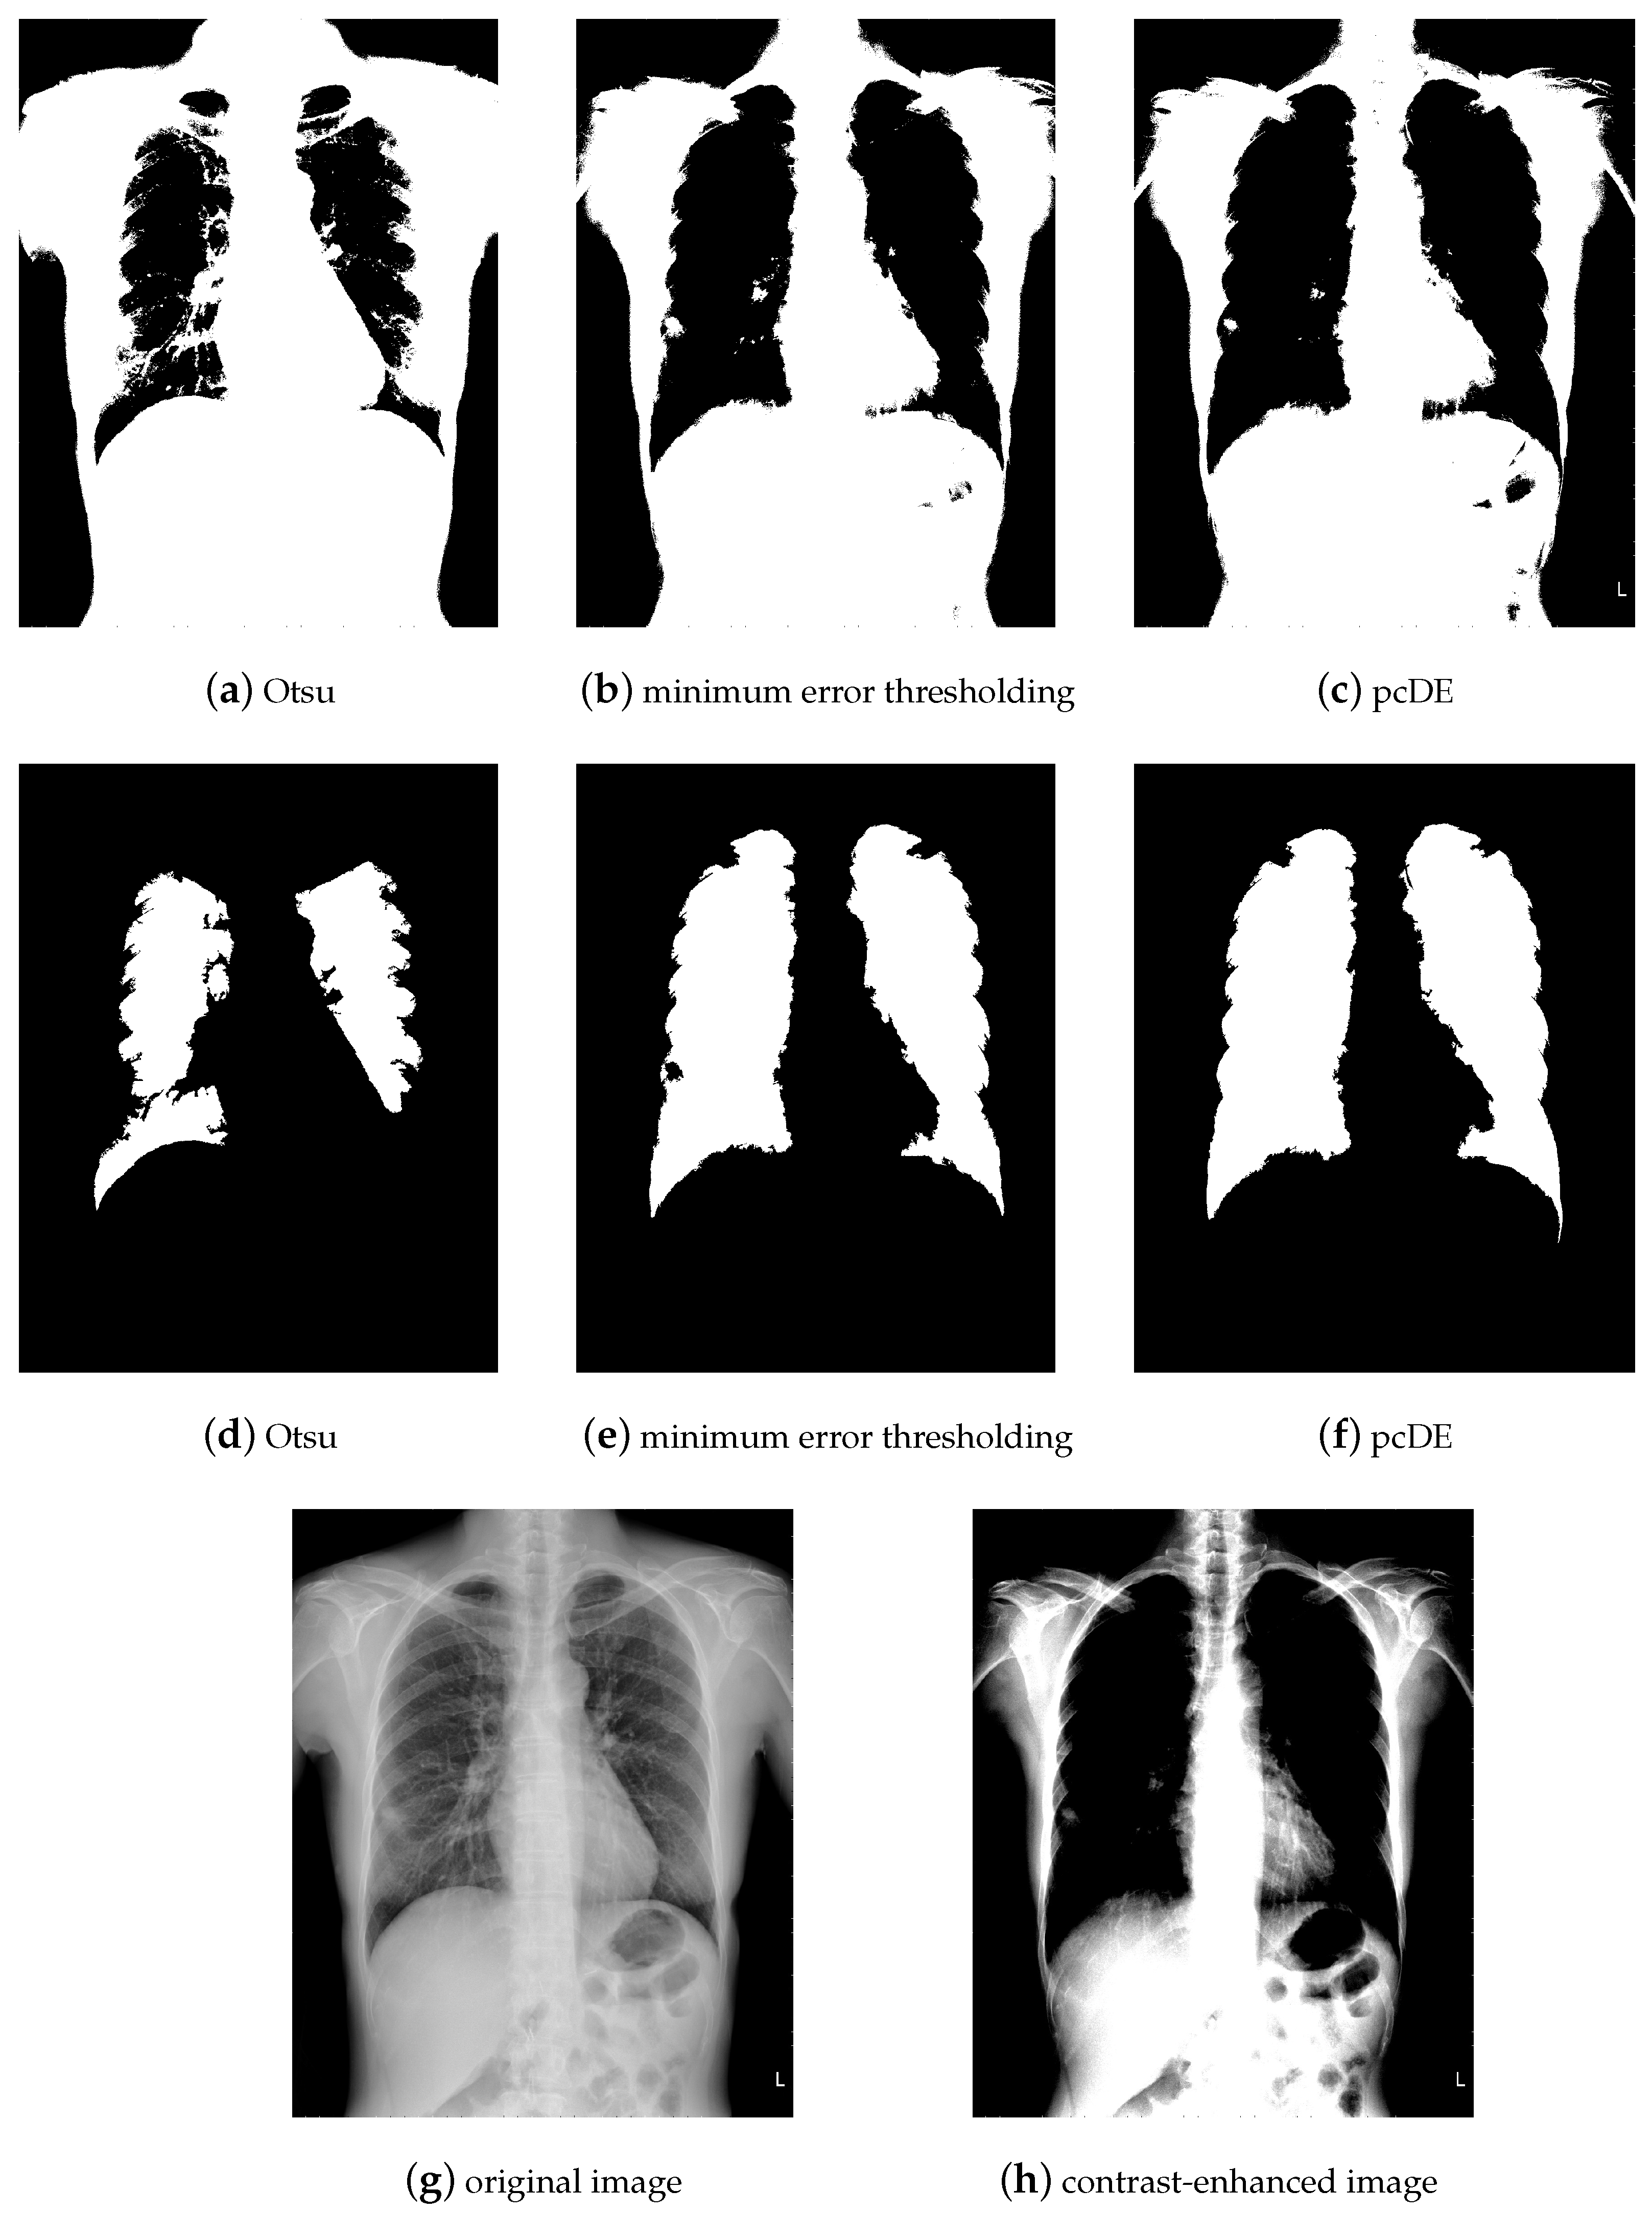

- Image preprocessing. Enhance the contrast of the image to achieve better segmentation.

- Calculate the optimal threshold for image segmentation through different methods to get the binarized image.

- Use morphological methods to process images to extract targets.

- Mark target contour.

- : Represent the result of ground truth segmentation (Figure 13).

- : Represent the result of algorithm segmentation.